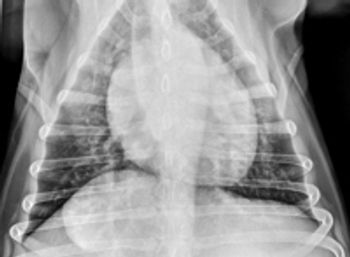

Megaesophagus is a condition in which the esophagus has reduced peristalsis, and has poor tone at rest. The esophagus can have a mild, focal motility problem, or the entire organ may be dilated and functioning poorly.